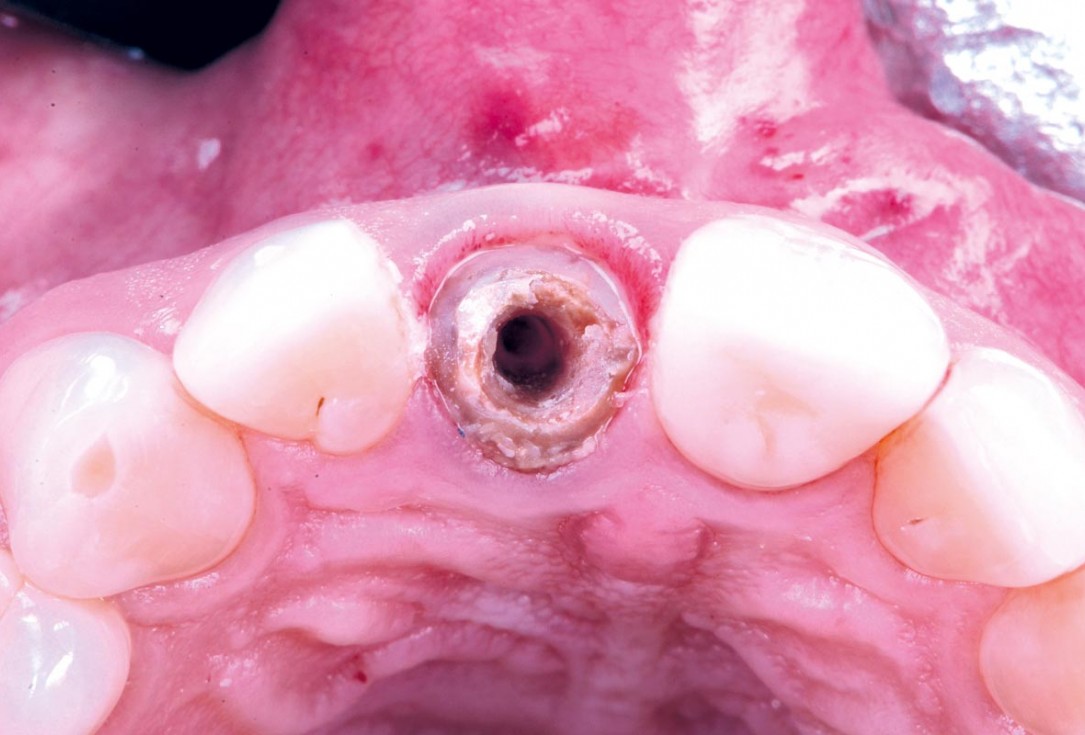

03/30 - Old crownExcellent aesthetic result of buccal augmentation with mucoderm® and maxgraft® after immediate implant placement - 3-years follow-up - Dr. A. Puišys

04/30 - Occlusal viewExcellent aesthetic result of buccal augmentation with mucoderm® and maxgraft® after immediate implant placement - 3-years follow-up - Dr. A. Puišys